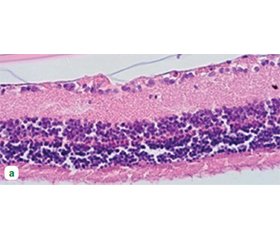

Актуальність. Вивчення механізмів діабетичної ретинопатії (ДР) має бути комплексним та включати оцінку різних взаємопов’язаних клітинних та молекулярних процесів, що ініціюються гіперглікемією. Мета дослідження: вивчити механізми розвитку початкової стадії ДР в експерименті з метою визначення основних та другорядних патологічних процесів у сітківці. Матеріали та методи. У щурів-самців лінії Wistar моделювали цукровий діабет і ДР шляхом одноразового введення стрептозотоцину (50 мг/кг; Sigma-Aldrich, Co, China). На 28-му добу експерименту проводили імуногістохімічне дослідження з використанням моноклональних антитіл проти гліального фібрилярного кислого протеїну (GFAP), нейронспецифічної енолази (NSE), тяжких нейрофіламентів, каспази-3 (ThermoFisher Scietific, США), протеїну S100 (Master Diagnostica, США) і васкулоендотеліального фактора росту (VEGF; Invitrogen, США). Результати. До ранніх проявів ДР відносилися набряк та розпушення шарів сітківки, дилатація венозного русла з явищами мікротромбозу, утворення дифузних зон ішемії, вогнища патологічного ангіогенезу (мікроаневризми), дегенерація гангліонарних клітин, розрідження ядерних шарів сітківки. Астроцити, клітини Мюллера та їх відростки активно експресували GFAP і протеїн S100, що свідчило про розвиток реактивного гліозу. Перенавантаження цих клітин кальцієм могло сприяти їх загибелі через апоптоз, що було підтверджено збільшенням експресії каспази-3. Суттєве збільшення експресії VEGF макроглією, відростки якої утворювали щільні муфти навколо капілярів сітківки, могло стимулювати патологічний ангіогенез. Розвиток нейродегенерації було підтверджено суттєвим зниженням експресії нейрофіламентів у шарах нервових волокон та збільшенням нейронального маркера пошкодження NSE. Висновки. Надмірна активація макроглії (реактивний гліоз) може вважатися першочерговою ланкою патогенезу ДР, корекція якої може доповнити анти-VEGF-терапію або застосовуватися окремо задля попередження розвитку ДР на ранніх етапах.

Background. The study of the diabetic retinopathy (DR) mechanisms should be comprehensive and include the assessment of various interconnected cellular and molecular processes initiated by hyperglycemia. The purpose was to study the mechanisms for the development of the initial stage of DR in an experiment in order to determine the main and secondary pathological processes in the retina. Materials and methods. Diabetes mellitus and DR were modeled in male Wistar rats by a single injection of streptozotocin (50 mg/kg; Sigma-Aldrich Co, China). On the 28th day of the experiment, immunohistochemical studies were performed using monoclonal antibodies to glial fibrillary acidic protein (GFAP), neuron-specific enolase (NSE), heavy neurofilaments, caspase-3 (Thermo Fisher Scientific, USA), S100 protein (Master Diagnostica, USA) and vascular endothelial growth factor (VEGF; Invitrogen, USA). Results. Early manifestations of DR included edema and detached retinal layers, dilation of the venous bed with microthrombosis, formation of diffuse zones of ischemia, foci of pathological angiogenesis (microaneurysms), degeneration of ganglion cells, retinal nuclear layer thinning. Astrocytes, Müller cells and their processes actively expressed GFAP and S100 protein, which indicated the development of reactive gliosis. Calcium overload in these cells could contribute to their death through apoptosis, which was confirmed by an elevated caspase-3 expression. A significant increase in the VEGF expression by macroglia whose processes formed tight couplings around the retinal capillaries could stimulate pathological angiogenesis. The development of neurodegeneration was confirmed by a significant decrease in the expression of neurofilaments in the nerve fiber layers and an increase in the neuronal damage marker, NSE. Conclusions. Excessive activation of macroglia (reactive gliosis) can be considered a primary link in the pathogenesis of DR whose correction can complement anti-VEGF therapy or be used separately to prevent the development of DR in the early stages.